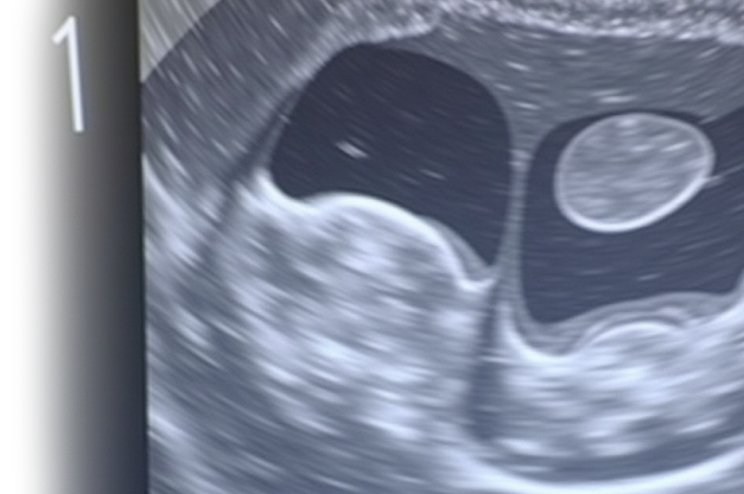

УЗИ органов брюшной полости с проведением водно-сифонной пробы – важный метод ультразвукового исследования, которое позволяет оценить состояние печени, желчного пузыря, поджелудочной железы, селезенки, желудка, кишечника и других органов брюшной полости.

При необходимости может быть проведена водно-сифонная проба, которая дает информацию о подвижности желчного пузыря и диагностировать его заболевания.

Само исследование проводится с помощью ультразвукового аппарата, который передает звуковые волны через ткани и получает обратное отражение от органов.